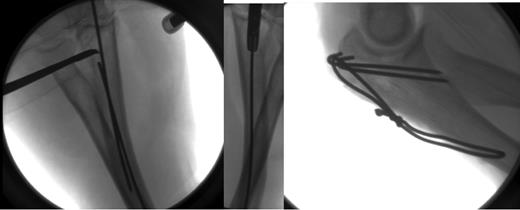

Ms R is a 68-year-old female who had a fall off a push bike and presented to the Emergency department with a comminuted fracture of the left olecranon. She was taken to theatre for an open reduction and internal fixation with a tension band wire construct. The fracture was reduced and held with two intramedullary K-wires. A hole was drilled in the proximal ulna to secure the cerclage wire distal to the fracture. During this process, the drill made contact with the K-wire and it was propelled distally within the intramedullary canal. On radiographic screening, the K-wire was sitting in the distal ulna. The wire was secured and removed with a set of artery clips (Fig. 1). Once removed, the fracture was re-reduced with two bicortical K-wires and a set of artery clips were used to secure them (Fig. 1).

Left—K-wire secured and removed with a pair of artery clips. Right—Final shots of the Tension band wiring construct.